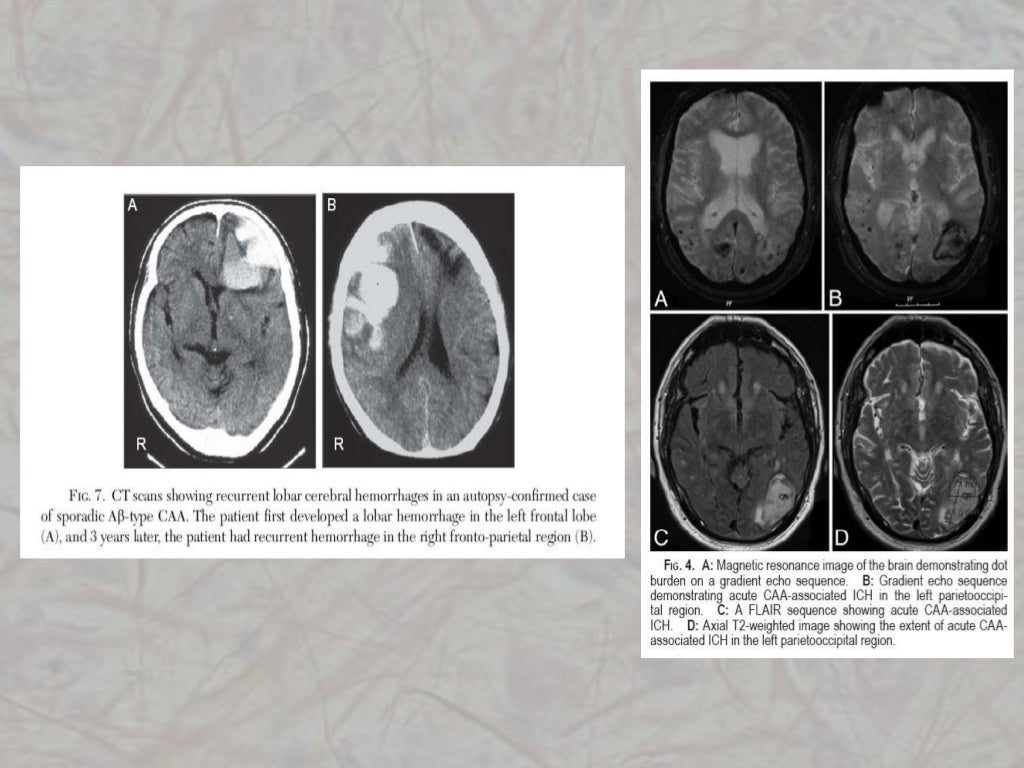

I depositi amiloidi predispongono a lesioni i vasi sanguigni coinvolti, aumentando il rischio di emorragie cerebrali; queste emorragie sono solitamente localizzate in un unico lobo cerebrale, a differenza delle emorragie legate all'ipertensione, e hanno un ampio range di manifestazioni cliniche: da asintomatiche, nel caso delle microemorragie, fino alle grandi emorragie che risultano in sintomatologie più evidenti ed invalidanti come emiparesi, aprassia.

La angiopatia amiloide può causare segni e sintomi molto diversi, la cui manifestazione principale è l'emorragia cerebrale. Emorragie più estese possono portare a conseguenze più serie come emiparesi, disturbi della coordinazione, afasia, aprassia, disturbi della sensibilità, e nei casi più gravi possono portare a morte. Per quanto riguarda le emorragie minori, non sono necessariamente associate a sintomi ma sono tuttavia visibili alla risonanza magnetica. Inoltre possono manifestarsi come alcuni episodi transitori, delle durata di qualche minuto, di deficit neurologici focali, caratterizzati a seconda dell'area interessata da: parestesie, debolezza o blocco ad un arto, perdita del campo visivo, macchie nel campo visivo e disturbi del linguaggio. Altrettanto possono verificarsi disturbi a livello cognitivo come afasia, disorientamento spaziale, deficit memoria a breve termine.

La diagnosi della forma non ereditaria si avvale dell'ausilio di una RM encefalica: qui vengono ricercati segni di emorragie, microemorragie o sanguinamenti pregressi. Applicando i "Criteri di Boston" può essere fatta diagnosi di Angiopatia amiloide "probabile" o "possibile", mentre la diagnosi di certezza può essere fatta solo con una biopsia, di solito eseguita post-mortem.